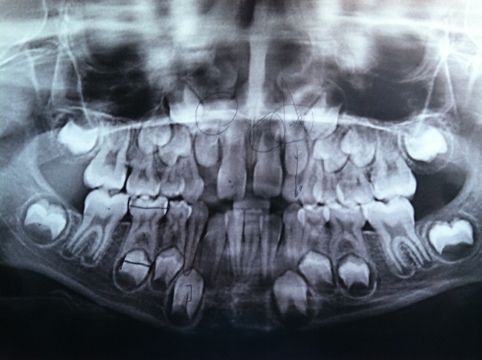

Posted on April 20, 2012April 20, 2012 by quinnjalanAlien What am I? Share this: Share on Facebook (Opens in new window) Facebook Share on X (Opens in new window) X Email a link to a friend (Opens in new window) Email Print (Opens in new window) Print Like Loading... Related

You are several extractions waiting to happen, followed by many tens of thousands of dollars worth of braces. Reply

You are several extractions waiting to happen, followed by many tens of thousands of dollars worth of braces.

Yup, right you are. I’ll be in poor house soon enough!